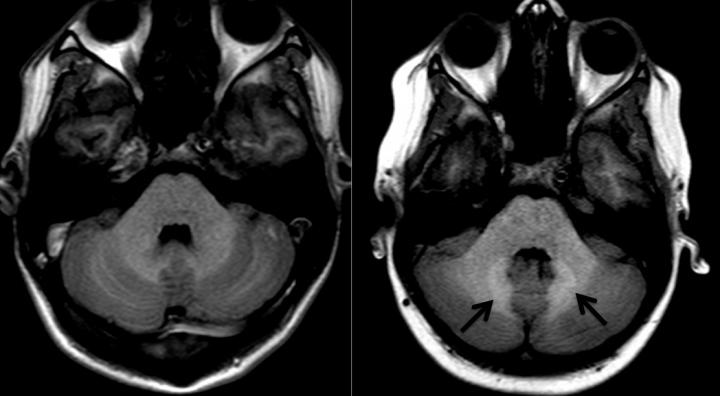

image: Arrows indicate areas of increased signal intensity (R) compared to normal control (L).

Investigators at Children's Hospital Los Angeles have determined that in children receiving gadolinium as a contrast agent to enhance MRI examinations, signal changes attributed solely to deposition of this material in the brain are not dependent on the amount of gadolinium administered but rather these changes are seen in association with other factors such as the presence of brain tumors and treatment using brain irradiation. Results of the study were just published in the journal, Radiology.

Tamrazi found that MR signal intensity changes presumed to be entirely secondary to gadolinium deposition in the brain were much more significant in patients who had primary brain tumors treated with radiation, independent of the dose of gadolinium they received. She suggests more research is needed to determine if brain tumor treatment with radiation enhances gadolinium deposition independent of the dose administered.